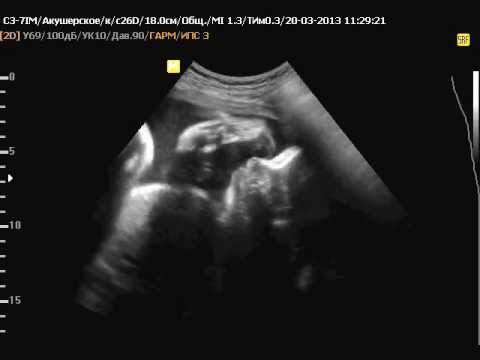

32 недели шевеления форум